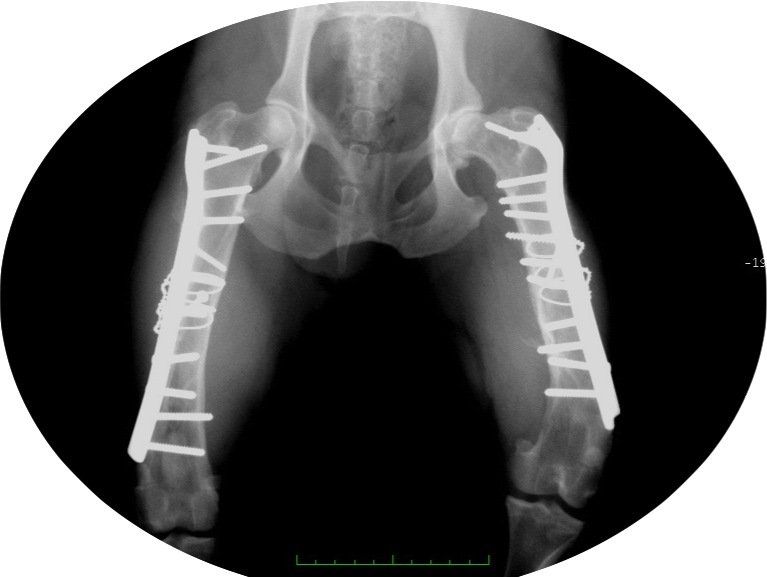

- reconstructive surgeries during broken bones limbs with the use of pins, plates and screws.